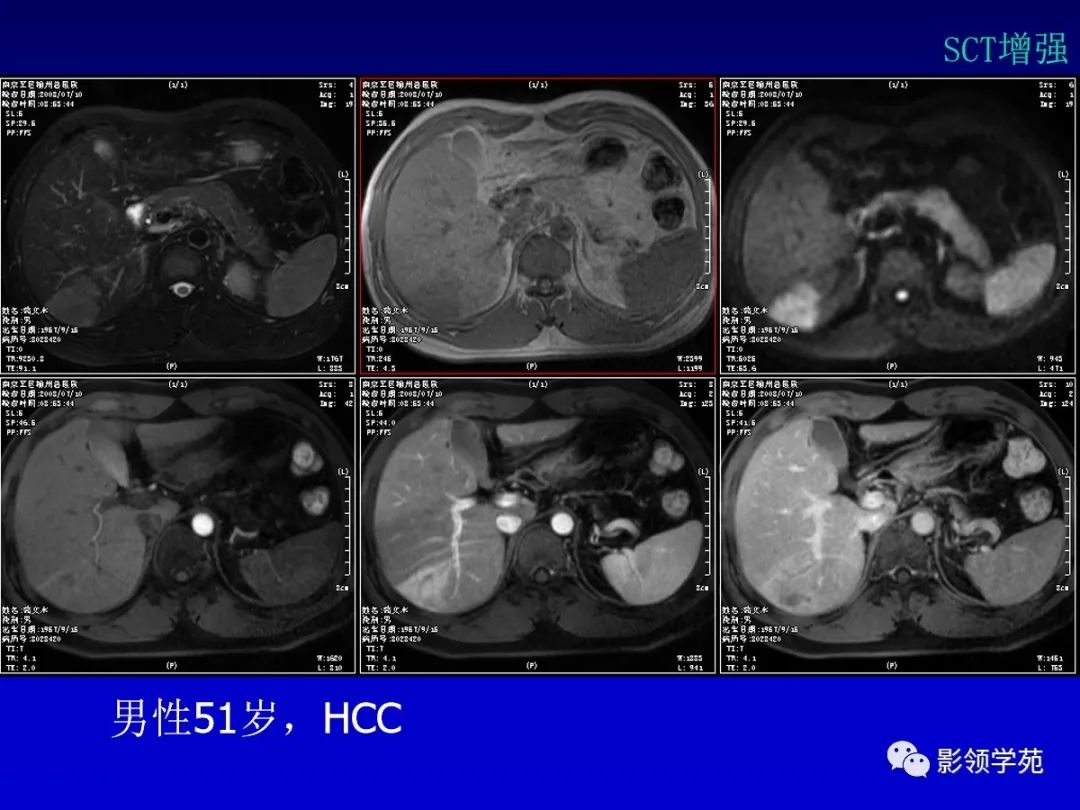

肝细胞肝癌(HCC)与胆管细胞癌(ICC)影像诊断要点